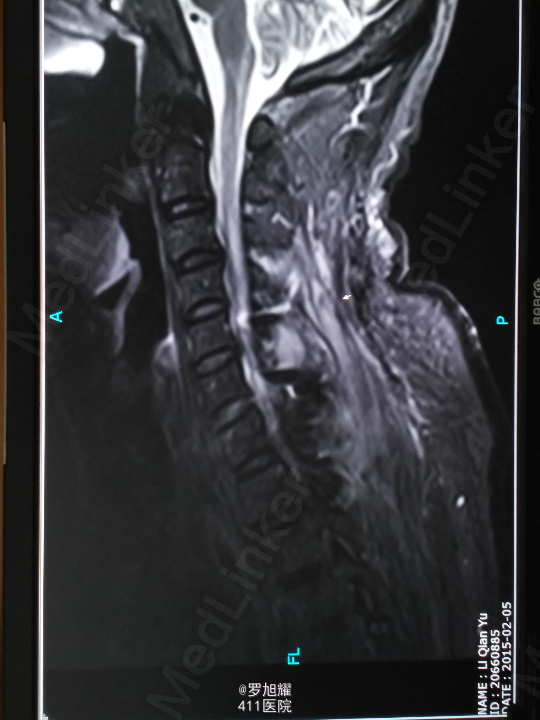

查体:双上肢前臂及以远感觉丧失,躯体自第二肋间平面以下感觉丧失。耸肩可,双侧三角肌、肱二三头肌肌力2级,腕关节屈伸、旋转及各指肌力0级。腱反射阴性,但球海绵体反射已经阳性。影像学检查示颈椎骨折脱位伴颈髓损伤。

诊断:颈6/7骨折脱位伴高位截瘫。处理:立即甲强龙冲击、脱水、保胃、营养神经治疗。首选治疗方案是颅骨牵引复位后前路融合固定,较后路稳定,出血也少,和家属谈话后开始颅骨牵引复位,4kg起步,每半小时增加1kg直至14kg,调整颈椎屈伸位,再加用手法牵引仍不能复位。改用备选方案,急诊行后路切开减压撬拨复位内固定,术后瘫痪症状部分改善。随访3月双上肢前臂及手部感觉恢复,仅双手掌尺侧及小指感觉障碍,双侧三角肌、肱二三头肌肌力4-5级,腕关节屈伸、旋转肌力左侧3级,右侧3-4级,但各指肌力仍0级。